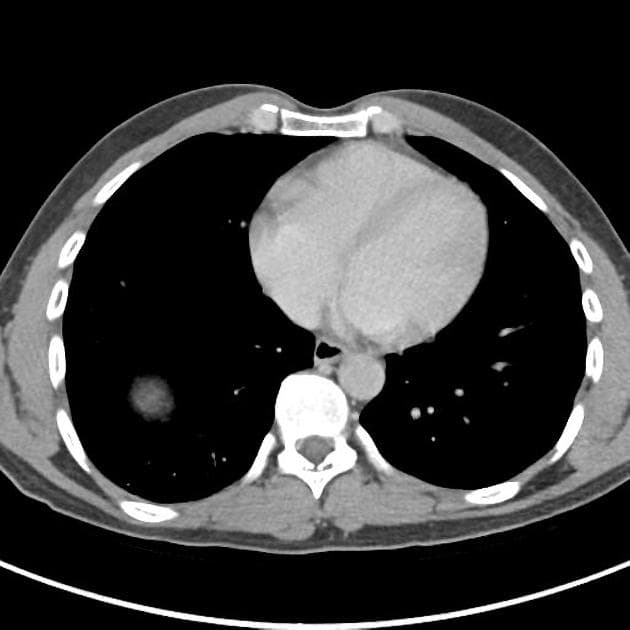

- Một khối ngấm thuốc kích thước 28 x 20 x 22 mm nằm ở phần trên của hệ thống đài bể thận phải.

- Trên cắt lớp vi tính (CT), tổn thương thường có mật độ mô mềm với mức độ ngấm thuốc nhẹ, thường thấp hơn đáng kể so với nhu mô thận hoặc ung thư tế bào ống thận.

- "Trên CT, ung thư biểu mô niệu quản thường cho mức độ ngấm thuốc nhẹ hơn nhu mô thận, giúp phân biệt với ung thư tế bào ống thận."

Ung thư tế bào biểu mô niệu quản thận khởi phát từ biểu mô chuyển tiếp của đài bể thận và được phân loại mô học là một dạng ung thư biểu mô niệu quản. Bệnh chiếm khoảng 5–10% các ung thư thận, hiếm gặp hơn nhiều so với ung thư tế bào ống thận. Trên CT có cản quang, tổn thương điển hình là khối mô mềm nhỏ trong đài bể thận với mức độ ngấm thuốc nhẹ đến trung bình. Do vị trí và đặc điểm ngấm thuốc không rõ rệt, khối u dễ bị bỏ sót, đặc biệt khi không có giãn đài bể thận. Chẩn đoán thường được nghĩ đến ở bệnh nhân tiểu máu không đau, nhất là những người có yếu tố nguy cơ như hút thuốc hoặc tiếp xúc nghề nghiệp với amin thơm. Chẩn đoán xác định cần dựa vào sinh thiết hoặc mẫu mô sau phẫu thuật. Điều trị chủ yếu là cắt thận – niệu quản toàn bộ kèm cắt vạt bàng quang, tùy theo giai đoạn bệnh và tình trạng bệnh nhân.